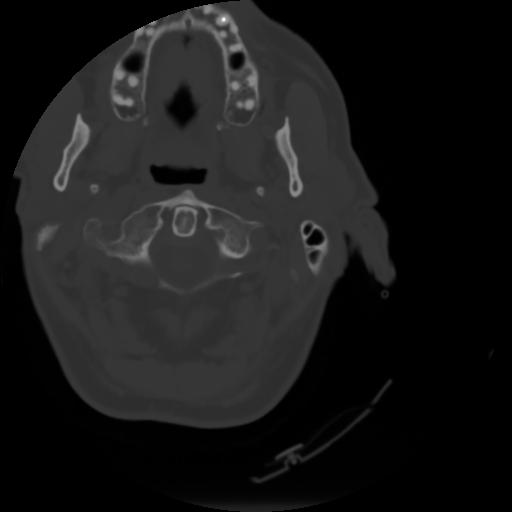

3 CEREBRO,,Axial,3.0,CEREBRO,,